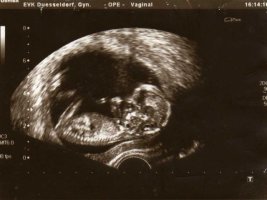

So jetzt versuch ich es mal mit den Bildern ^^

Das Ultraschallbild ist noch von November =)